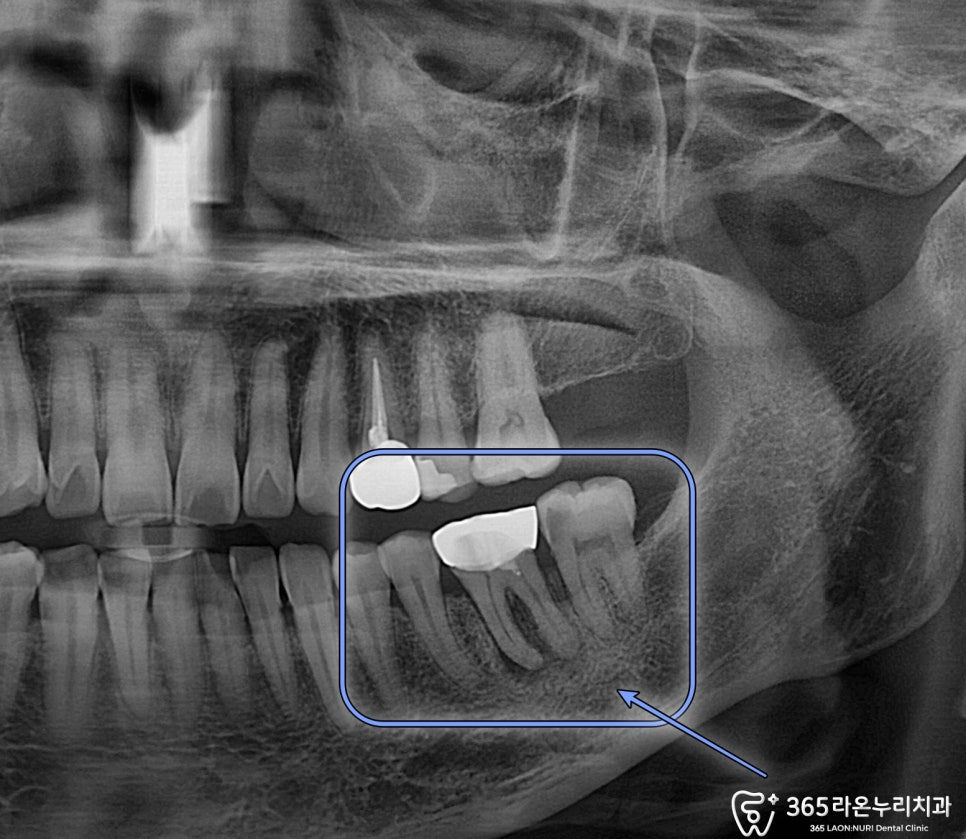

위 보여드리는 사진을 보면

치료했던 보철 아래로 잇몸

염증이 생긴 모습을 볼 수 있습니다.

또 주변 치아들은

심한 우식증이 발생하였는데요.

파노라마 엑스레이 사진을 보면

치조골쪽 염증으로 인한

광범위한 치조골 소실 양상이

관찰되었습니다.